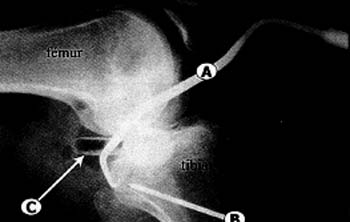

Foto n° 11: Secuencia artroscopica. A: Con el shaver se inicia la capsulotomia, desde proximal a distal. B: Vision desde la via posterointerna, ya realizada la capsulotomia se observan las fibras de color rojo del musculo popliteo. C: Colocación de la gula tibial en el fondo del sulcus tibial. D: Control bajo vision continua de la salida del pin y la mecha.

08_01_01_img12

Foto n° 12: Radiografia intraoperatoria. A: rama de guia tibial. B: Entrada del pin en la tibia desde distal a proximal. C: Canula de instrumentacian colocada en la via posterointerna.

Para controlar la correcta colocacion de la gufa el use de la radioscopia intraoperatoria es de gran utilidad (Fig. 12).(9,11,20,31)